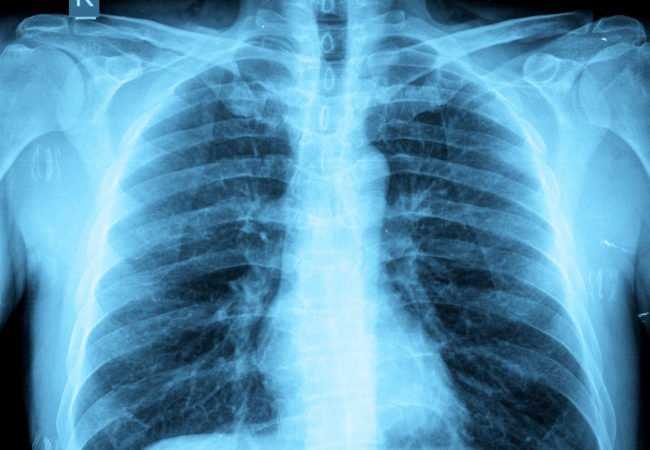

Γνωρίζουμε όλοι πως η παχυσαρκία μπορεί να είναι καταστροφική για την υγεία μας με πολλούς τρόπους. Τώρα, νέα έρευνα Βρετανών επιστημόνων δείχνει πως οι παχύσαρκοι άνθρωποι κινδυνεύουν περισσότερο να εμφανίσουν καρκίνο από τις ακτινογραφίες. Η επιστήμη εξηγεί γιατί.

Όπως διαπίστωσαν ο επικεφαλής της έρευνας, Dr. Saeed Al-Qahtani και οι συνεργάτες του, οι παχύσαρκοι άνθρωποι δέχονται μεγαλύτερη δόση ακτινοβολίας όταν κάνουν ακτινογραφίες προκειμένου να φανεί το αποτέλεσμα. Έτσι, έχουν και 154% περισσότερες πιθανότητες να εμφανίσουν καρκίνο.